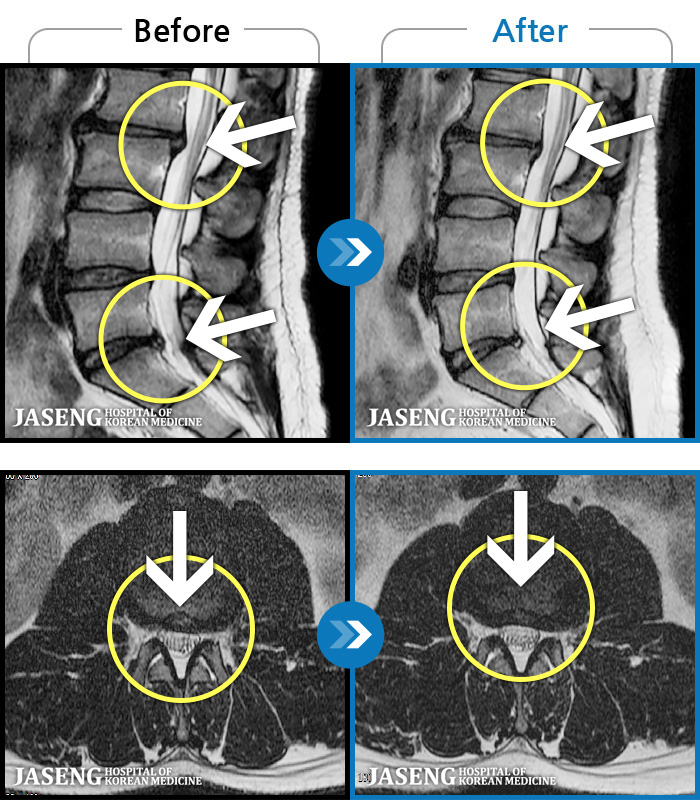

MRI ġ

1,237 MRI ũ ʸ Ȯϼ.

[Ȼ_㸮ũ] 㸮 ְ ٸ ȱⰡ .

[_㸮ũ] 㸮 , ٸ ̾ ϼ̽ϴ.

[õ_㸮ũ] ߲ 㸮 , ٷ

[ϻ_㸮ũ] ݺ ӵǸ ڼ ÿ ȭǴ ߵ ̻ ȣϴ ¿ϴ.

[ϻ_㸮ũ] ؽϰ ߰ ̴ · ϻȰ ¿ϴ.

[ؿ_㸮ũ] 㸮 ϰ

[_㸮ũ] 㸮 ߰ Ͽ ϼ̽ϴ.

[_㸮ũ] Ƹ ߱ ̾ ϼ̽ϴ.

[_㸮ũ] 㸮 ݱ , ٸ Ͽ ϼ̽ϴ.